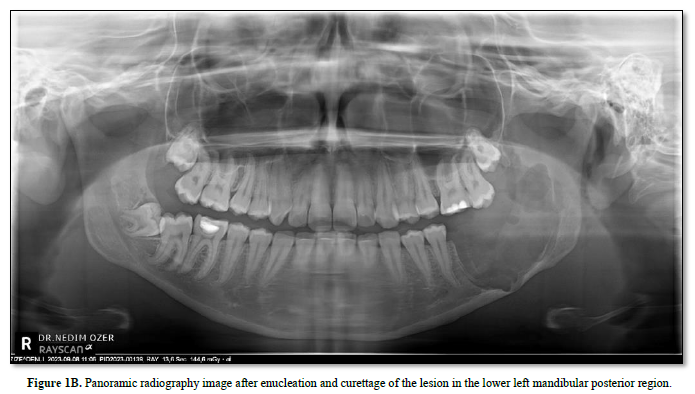

After local anesthetic agents were applied to the lesion area, a winter-style intraoral incision was made from the mesial of tooth number 34 to the margo anterior region of the ramus with the help of a scalpel. A full-thickness mucoperiosteal flap was raised and the lesion was accessed. Tissue with mucous consistency, myxoid structure and no bleeding was enucleated. Tumor-related teeth 36 and 37 were extracted while preserving the mandibular nerve. The obtained specimen was sent for pathological examination again for confirmation. The surgical area was closed primarily with 4-0 pegalac suture.

In the latest classification, WHO removed ameloblastic fibro-odontoma from the classification, considering it as an intermediate developmental stage of a tumor developing from ameloblastoma to odontoma. In this case, considering that we examined the entire tumor and that the dental hard tissue is seen in a very small focus and that fibroma and odontogenic-ameloblastic epithelium are determinants of morphology, it can be said that the prognostic process will be compatible with "Ameloblastic Fibroma" (Figures 1-3).